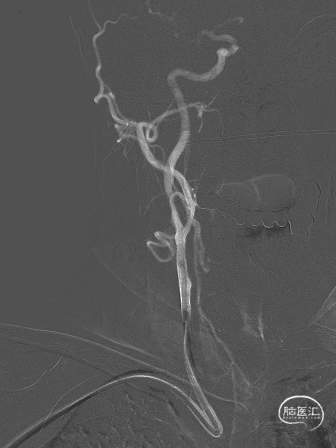

扩张完毕后多角度造影显示狭窄较前明显改善(箭头处)。

撤出保护伞观察10分钟复查造影,无弹性回缩,狭窄明显好转,血流明显改善(箭头处),结束手术。